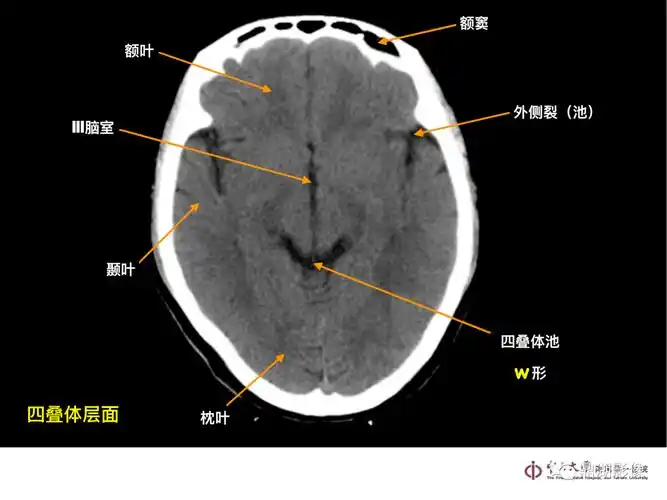

一套非常牛的「头颅ct解剖图谱」

头颅ct 解剖图谱,人手一份

头颅ct解剖与常见出血梗死判读

头部ct影像解剖